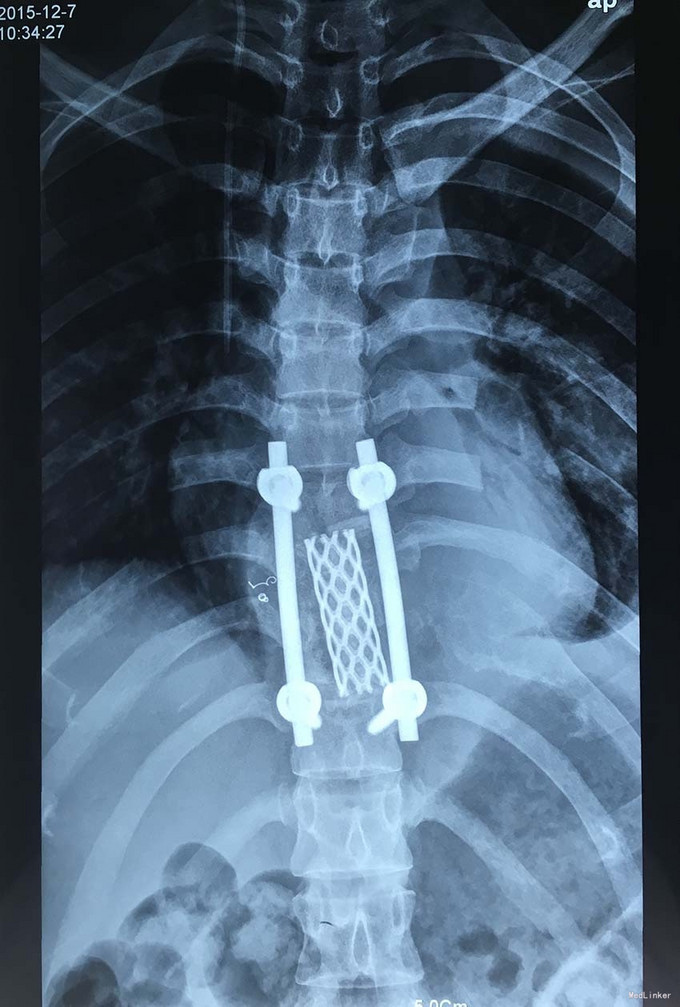

诊断:胸椎椎体肿瘤(T9-10) 治疗:先于外院行1期后路椎弓根钉固定融合手术,然后转入我院行介入下术前椎体节段血管栓塞手术,第二天行经左侧胸腔入路椎体肿瘤病灶刮除并钛网植骨植入重建手术。术后恢复满意。复查MRI显示肿瘤病灶基本完全切除。